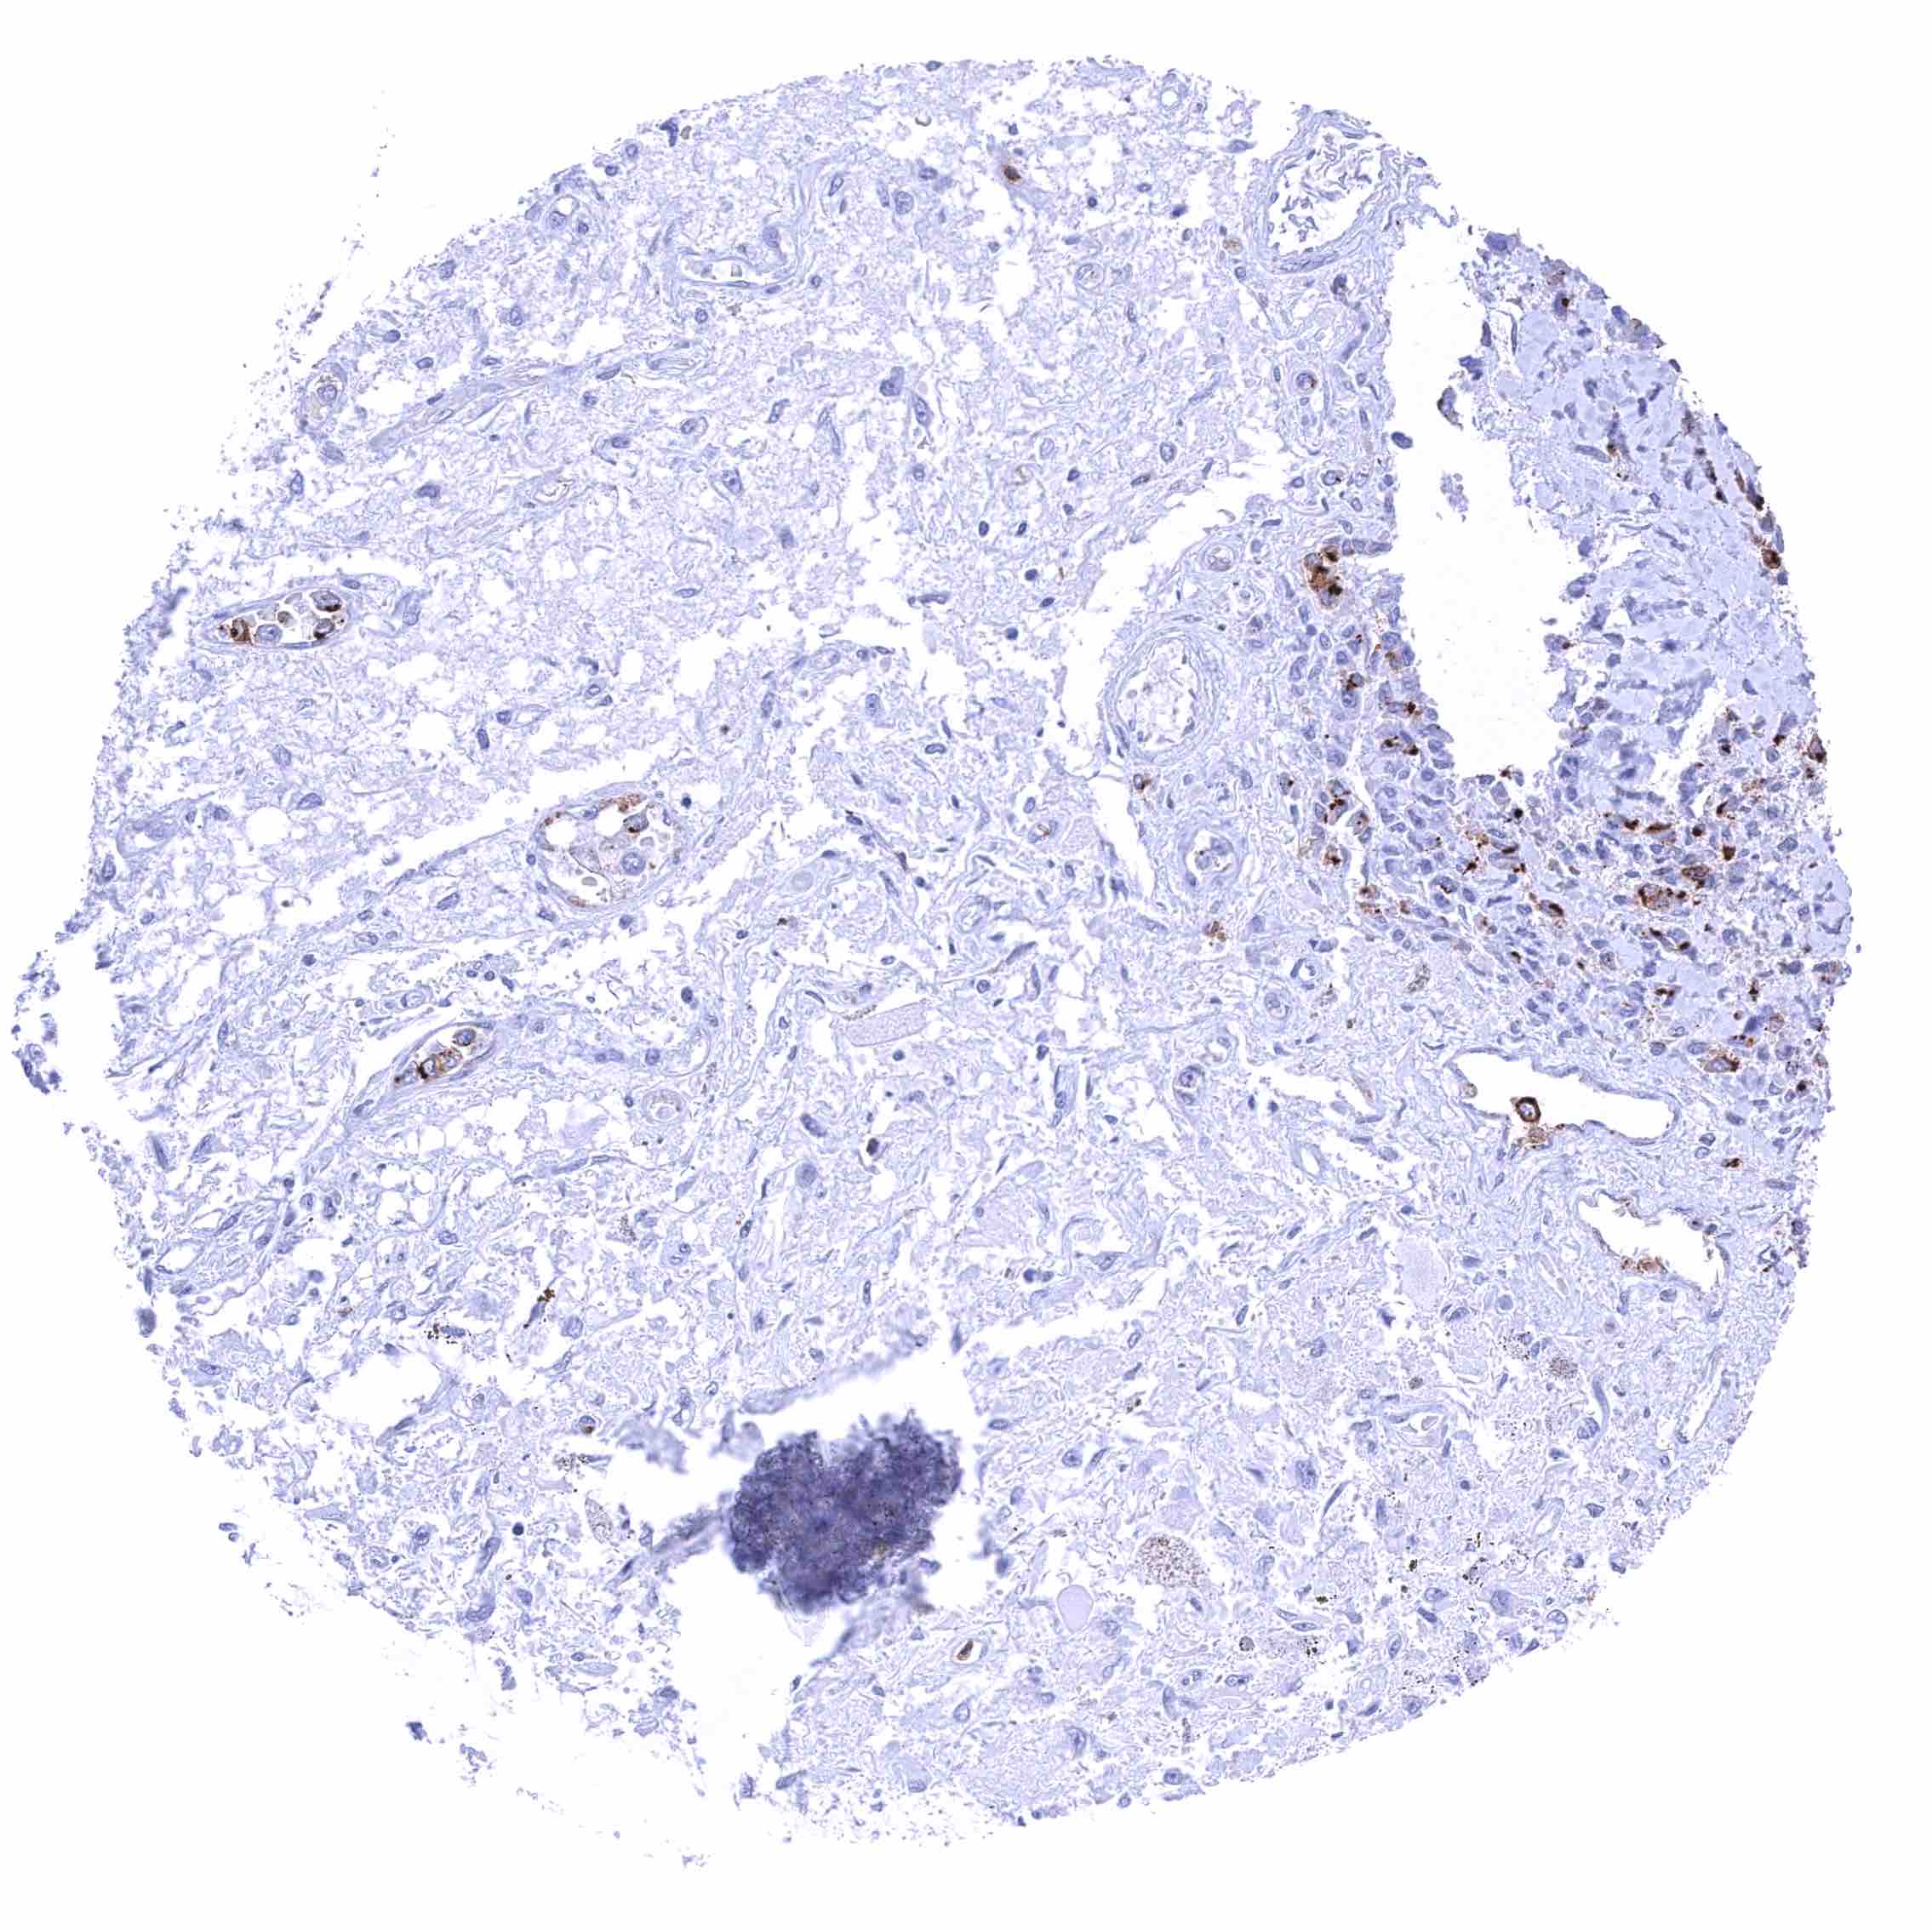

Kidney, cortex – Distinct CD70 membranous staining of the parietal layer of the Bowman capsule and of the luminal surface membrane of few tubuli which appear atrophic.

Kidney, cortex